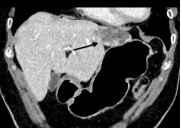

患者李先生(化名),因上腹部不适来我院就诊。经过彩超、腹部增强CT等详细检查,发现肝左叶有两枚血管瘤。较大一枚位于肝脏边缘包膜下且体积较大,瘤体直径将近6cm ,一旦发生破裂,后果不堪设想。

针对患者的病情,介入放射科团队与内二科医务人员进行了全面的评估和讨论。考虑到患者肝血管瘤最大直径大于5cm并位于包膜下,符合手术指征,本着手术微创化原则,跟患者及家属进行充分沟通后,最终决定为患者实施肝血管瘤肝动脉栓塞术介入治疗。